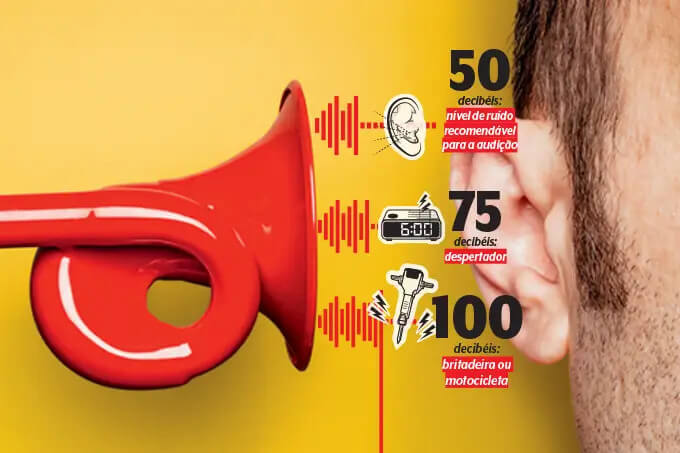

Fones de ouvido podem causar riscos para a audição; saiba como usar com segurança.

O uso incorreto e irrestrito pode comprometer para sempre a saúde de crianças e jovens. É preciso cuidado!

Saúde auditiva de crianças e jovens se agrava na pandemia com uso incorreto e irrestrito de fones de ouvido

Como saber se o volume está alto demais e quando fazer pausas? Fernando Balsalobre, otorrinolaringologista, dá dicas da utilização de fones de ouvido com segurança

Poluição sonora: um problema do barulho (e de saúde pública)

Não é força de expressão! A exposição a sons altos ou constantes não corrói apenas a audição. Ameaça a cabeça e o coração

Fones de ouvido: Saiba quais são os riscos que o dispositivo traz à audição

Uso incorreto de fones de ouvido pode comprometer a saúde de crianças e jovens